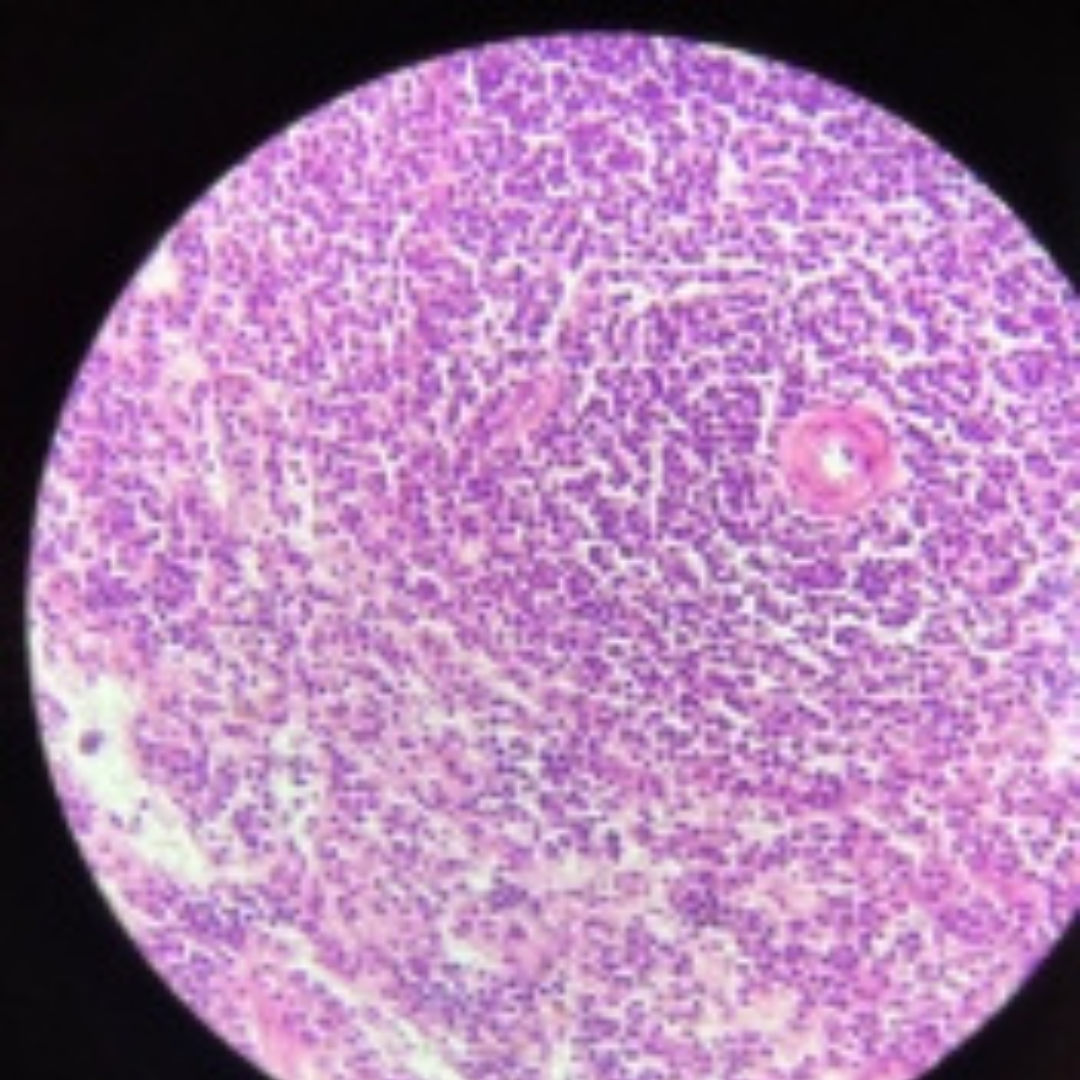

Thymus

33

New cards

Thymus

34

New cards

Thymus

35

New cards

Thymus (Involuted)